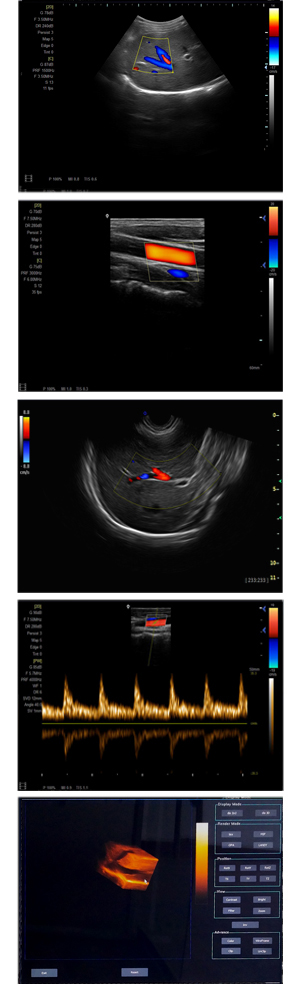

為高集成數(shù)字式彩色多普勒系列產(chǎn)品之一,廣泛實(shí)施于腹部,產(chǎn)科,婦科,血管,小器官,泌尿,新生兒和兒科等臨床,屬全身應(yīng)用型彩色多普勒儀器。

●全身應(yīng)用型包含2D/CFM/PDI/PW/ M等掃描模式;

●升級版可選配3D、反向諧波等高級功能。